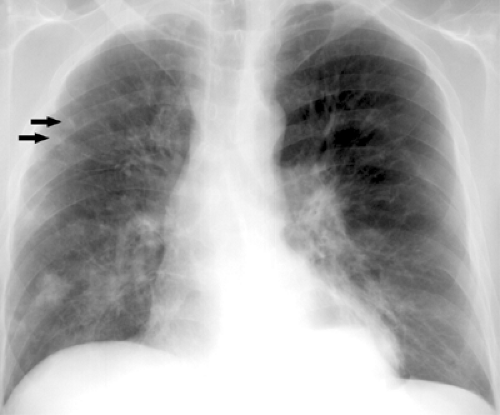

Рентгенодиагностика бронхопневмонии: Советы и примеры

Раздел: Альбом открытий